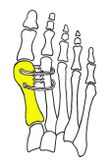

Syndesmosis procedure addresses specifically the two fundamental problems of metatarsus primus varus deformity that gives rise to the bunion deformity. They are leaning and instability of the first metatarsal bone . Syndesmosis procedure uprights the leaning first metatarsal bone with strong binding sutures between it and the second metatarsal bone (Fig. 2) and then also stabilizes it uniquely by creating a fibrous connecting bridge between these two bones (Fig. 3, 4). First metatarsal bone can be readily realigned because by definition of the metatarsus primus varus deformity its first metatarsal is abnormally loose and mobile.[citation needed]